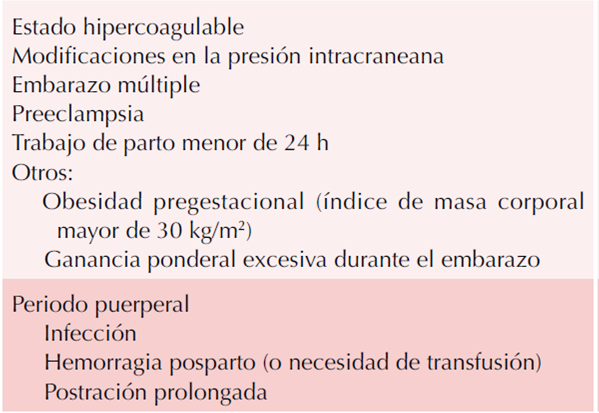

Durante el embarazo, los cambios en el flujo venoso inducidos hormonalmente, la obstrucción mecánica por el útero,4 el incremento de los procoagulantes, como el fibrinógeno, factores XII, VIII, X, von Willebrand, la adhesión plaquetaria, el plasminógeno activador inhibidor-1 (con disminución de fibrinólisis) y 2, aumentan el riesgo de trombosis venosa cerebral. (Cuadros 3 y 4) De igual manera, disminuye la acción anticoagulante de la proteína S libre3 y aumenta la resistencia a la proteína-C activada.5 En el trascurso del puerperio, el estado máximo de hipercoagulabilidad4 se considera el periodo con mayor riesgo de un episodio de tromboembolismo.6 La infección, deshidratación por pérdidas sanguíneas durante el parto y la postración prolongada también son causas que pueden predisponer a una trombosis venosa cerebral. Si bien la preeclampsia-eclampsia coexistente puede aumentar las afecciones cerebrovasculares, como la isquemia y la hemorragia intracerebral, se relaciona en menor grado con trombosis venosa cerebral.2 Ésta se relaciona con interrupción de la barrera hematoencefálica, edema vasogénico y áreas focales de alteración del drenaje venoso.7 Está reportado que, en algunos casos, la etiología de la trombosis venosa cerebral puede relacionarse con la punción lumbar o la pérdida de líquido cefalorraquídeo. Los factores de riesgo identificados en el caso que se comunica fueron: periodo de puerperio e interrupción por cesárea con punción lumbar para anestesia regional, postración prolongada, preeclampsia severa, dos embarazos e interrupción por cesárea.